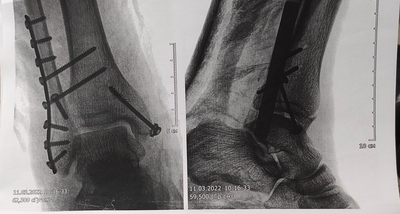

19 февраля этого года сломал ногу. Трехлодыжечный перелом+ остиосинтез(установка металла в ногу).